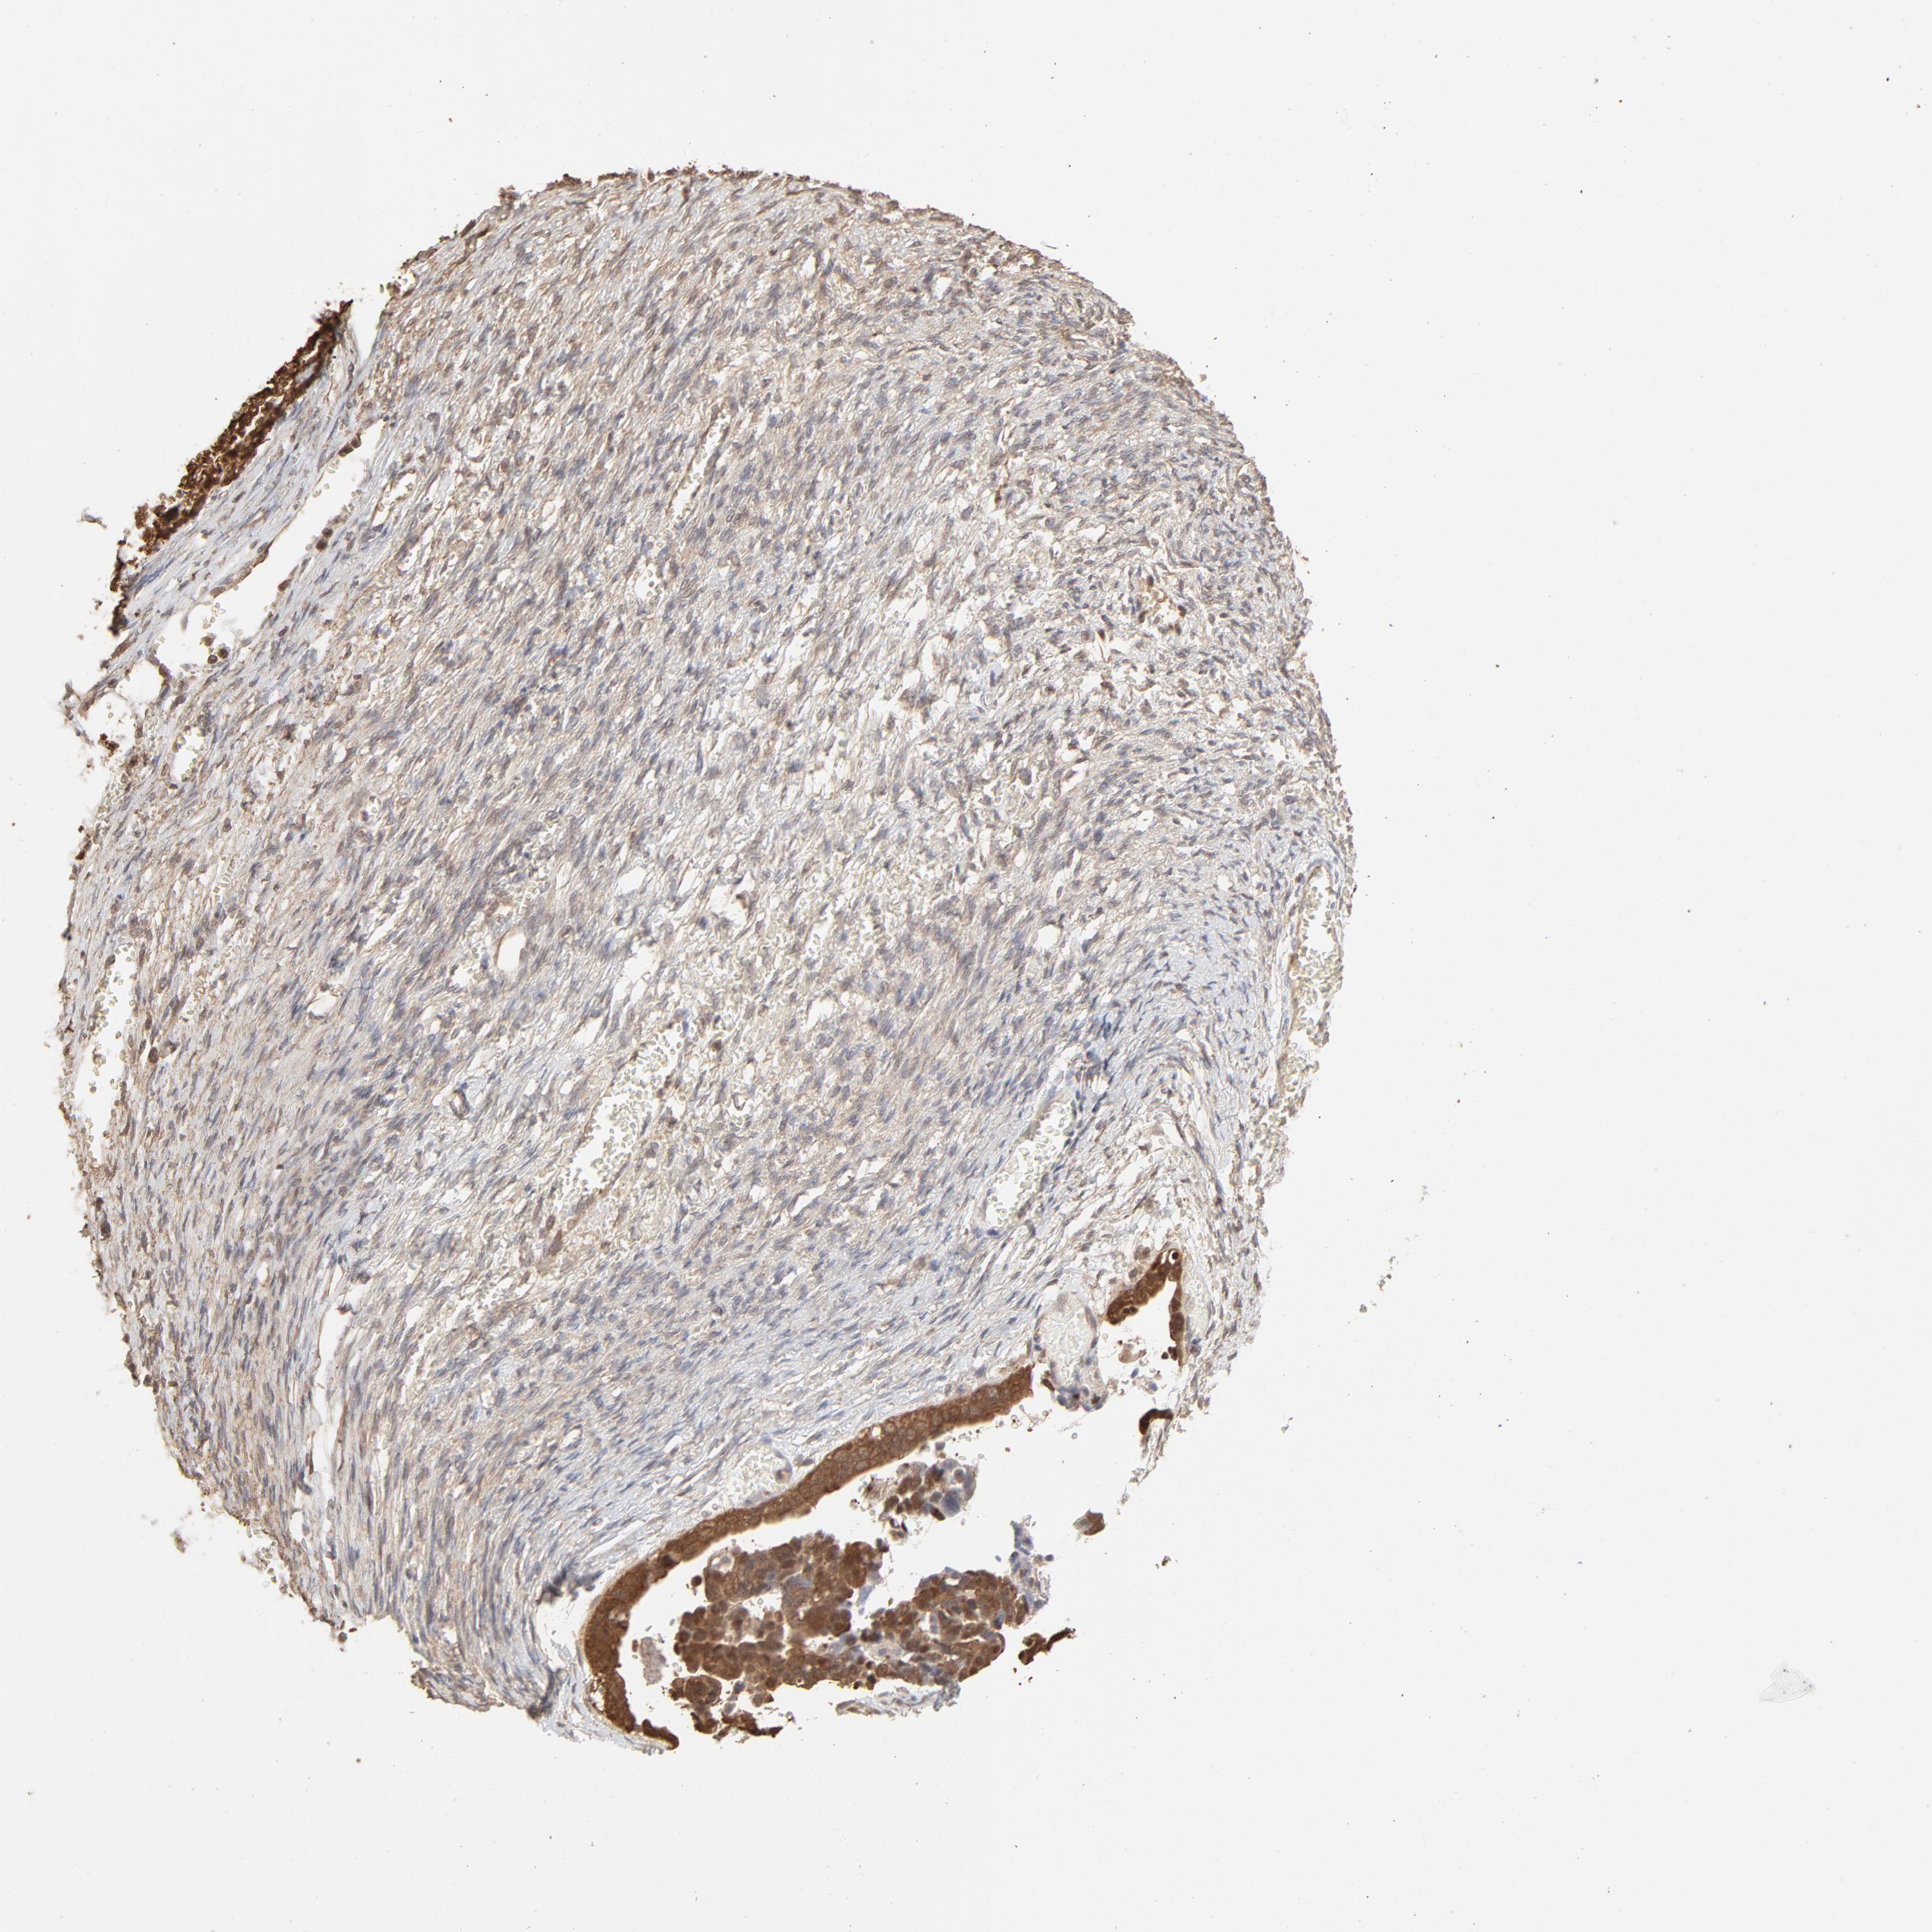

OVARIAN CANCER - Protein expressioni

A mouse-over function shows sample information and annotation data. Click on an image to view it in a full screen mode. Samples can be filtered based on level of antibody staining by selecting one or several of the following categories: high, medium, low and not detected. The assay and annotation is described here.

Note that samples used for immunohistochemistry by the Human Protein Atlas do not correspond to samples in the TCGA dataset.

Antibody stainingi

Antibody staining in the annotated cell types in the current human tissue is reported as not detected, low, medium, or high, based on conventional immunohistochemistry profiling in selected tissues. This score is based on the combination of the staining intensity and fraction of stained cells.

Each image is clickable and will lead to virtual microscopy that enables deeper exploration of all samples and also displays staining intensity scores, fraction scores and subcellular localization as well as patient and tissue information for each sample.

Antibody HPA043236

Antibody CAB003848

Cystadenocarcinoma, serous, NOS

Carcinoma, endometroid

Cystadenocarcinoma, mucinous, NOS

Carcinoma, NOS